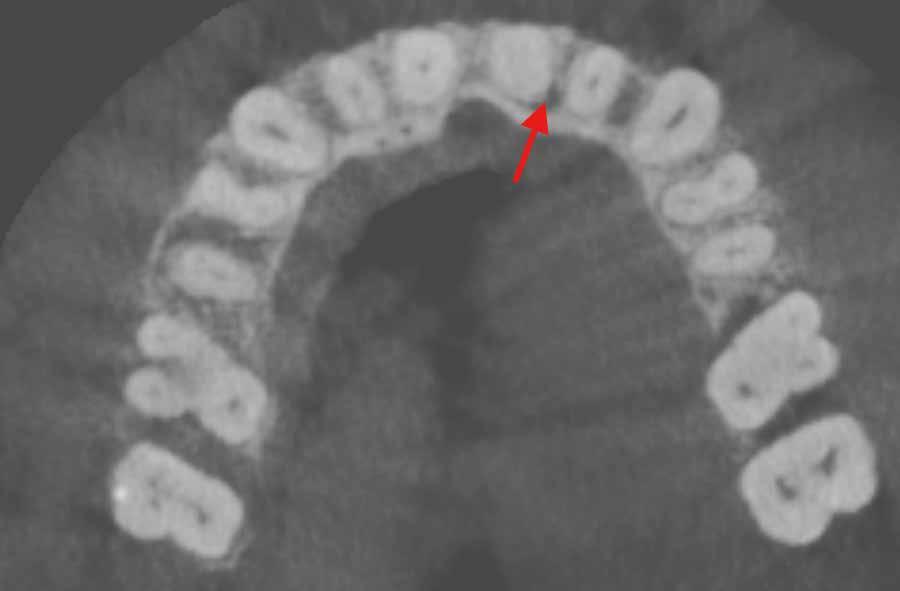

The patient returned in May 2024 reporting a history of slight discomfort

from the tooth. In the intervening two years, the patient’s dentist had applied a composite build-up, secured using two pins, making the UL1 heavily restored. A new CBCT scan showed severe calcification of the root canal, and a lateral radiolucency mid-root on the distal aspect (marked with red arrow) (Figure 2).